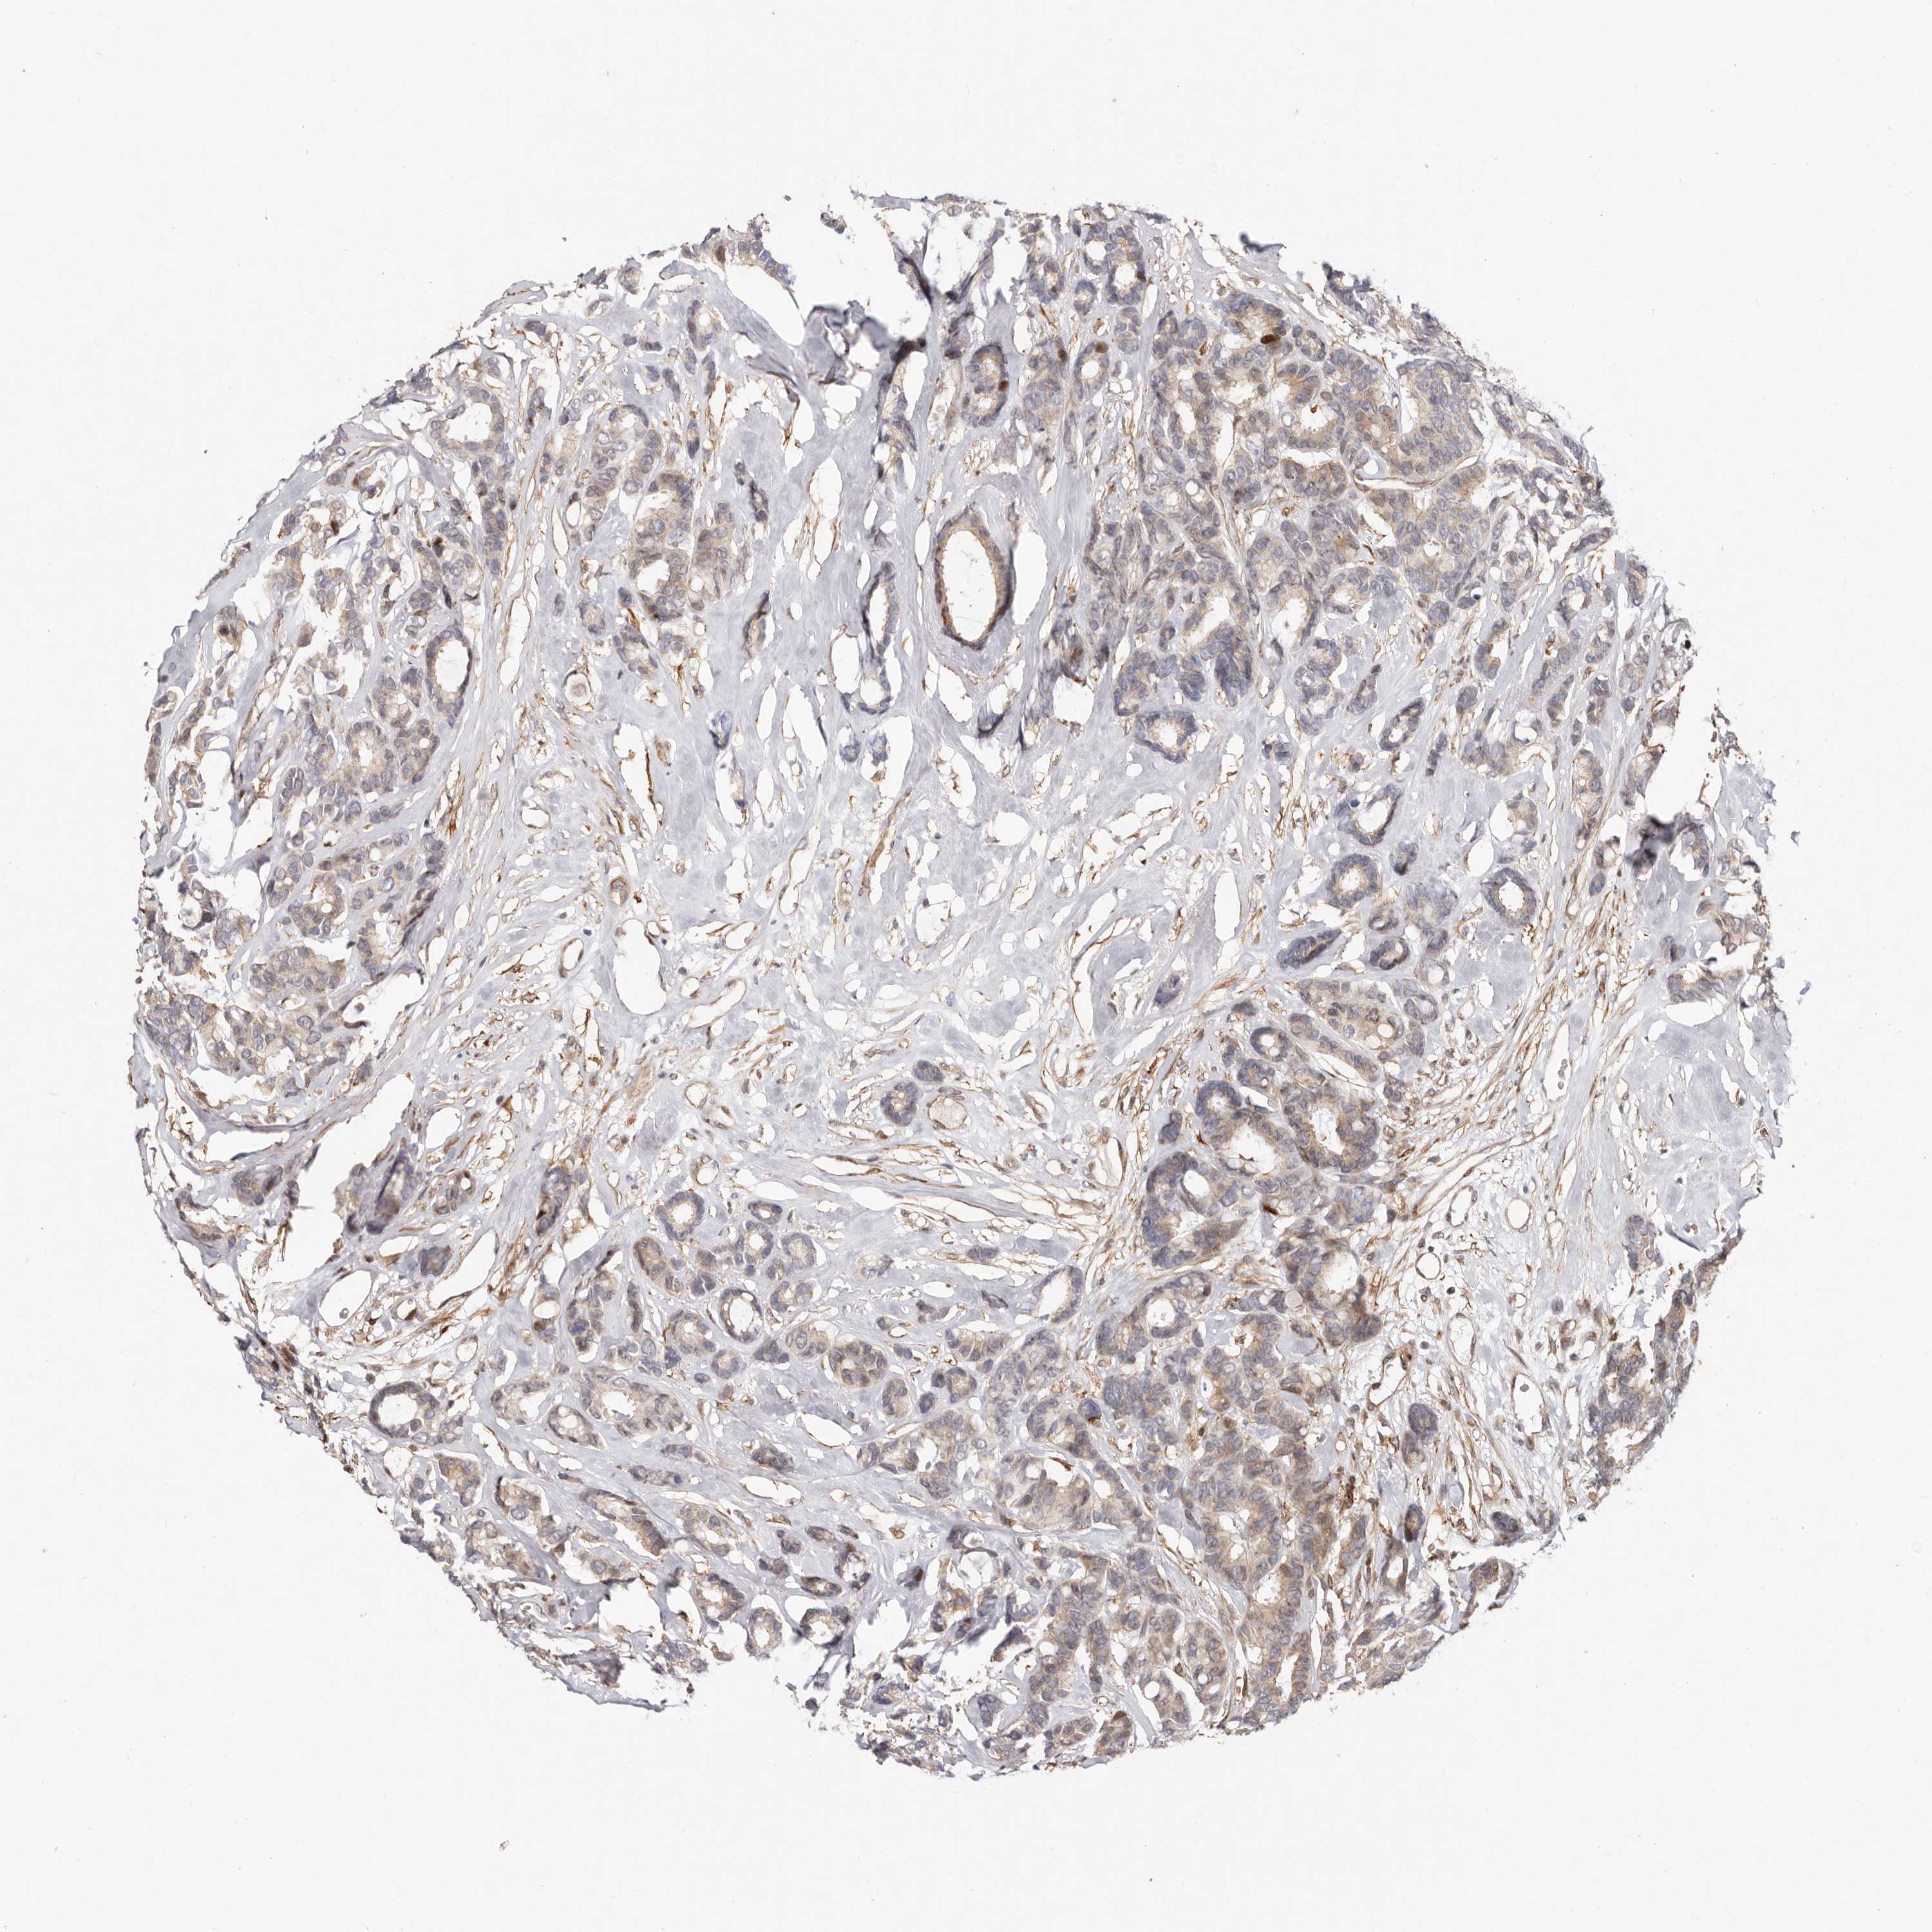

CANCER BREAST CANCER Show tissue menu

BRCA TCGA BRCA VALIDATION PROTEIN EXPRESSION

Breast cancer

Human cancer